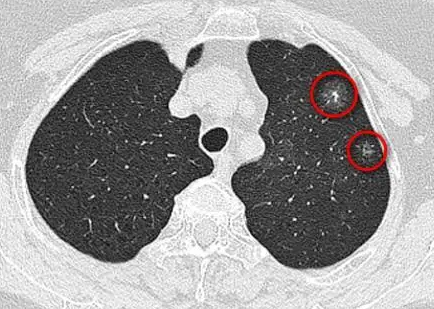

肺内边界模糊或清楚的无一定形状的密度增高影,其内可见血管纹理及支气管壁,因为样子像磨砂玻璃,所称为磨玻璃影(GGO),按照范围分为局灶性和弥漫性。

而以磨玻璃影(GGO)为主要特点的肺部结节就称为磨玻璃结节(GGN),磨玻璃样结节是一种在肺部 CT 薄层扫描上发现的病变。在临床上,根据结节的“透明度”,可以将磨玻璃结节分为

单纯性磨玻璃结节:此类病灶呈现在医学影像学上比较均匀;

混合型磨玻璃结节:此类病灶在医学影像学上表现为“透明度不均”,部分不透明;

实性型磨玻璃结节:这类病灶在医学影像学上表现几乎不透明。

有很多种肺部疾病可以在 CT 上成为此类表现,最常见的是炎症以及一部分早期肺癌。“透明度”不同,疗效差异大。而这三类肺癌的I期患者5年生存率可分别达到100%、87.6%和73.2%。